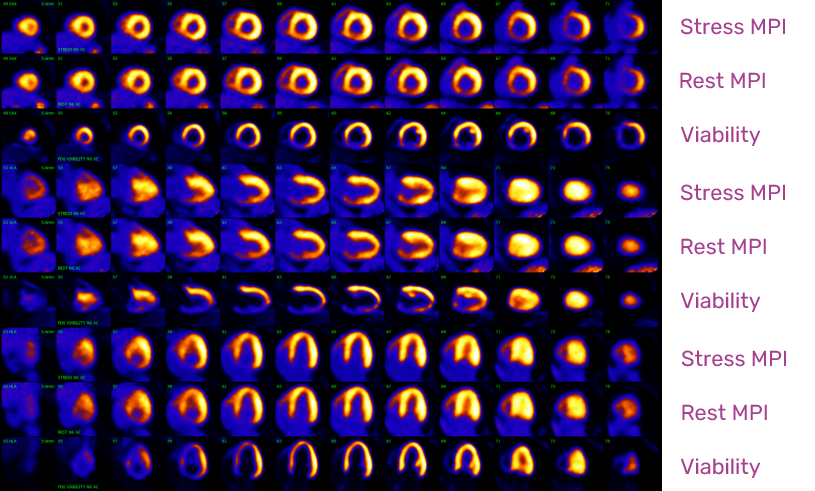

Cardiac Pet/ct

Enhance your business with our stunning commercial Cardiac Pet/ct collection of numerous professional images. optimized for commercial use with truck, vehicle, and automobile. ideal for corporate communications and branding. Discover high-resolution Cardiac Pet/ct images optimized for various applications. Suitable for various applications including web design, social media, personal projects, and digital content creation All Cardiac Pet/ct images are available in high resolution with professional-grade quality, optimized for both digital and print applications, and include comprehensive metadata for easy organization and usage. Discover the perfect Cardiac Pet/ct images to enhance your visual communication needs. Our Cardiac Pet/ct database continuously expands with fresh, relevant content from skilled photographers. Reliable customer support ensures smooth experience throughout the Cardiac Pet/ct selection process. Professional licensing options accommodate both commercial and educational usage requirements. Multiple resolution options ensure optimal performance across different platforms and applications. Regular updates keep the Cardiac Pet/ct collection current with contemporary trends and styles. Each image in our Cardiac Pet/ct gallery undergoes rigorous quality assessment before inclusion. Time-saving browsing features help users locate ideal Cardiac Pet/ct images quickly. The Cardiac Pet/ct archive serves professionals, educators, and creatives across diverse industries. Comprehensive tagging systems facilitate quick discovery of relevant Cardiac Pet/ct content.